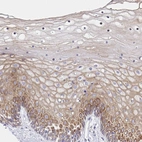

Immunohistochemical staining of human cervix, uterine shows moderate cytoplasmic positivity in squamous epithelial cells.